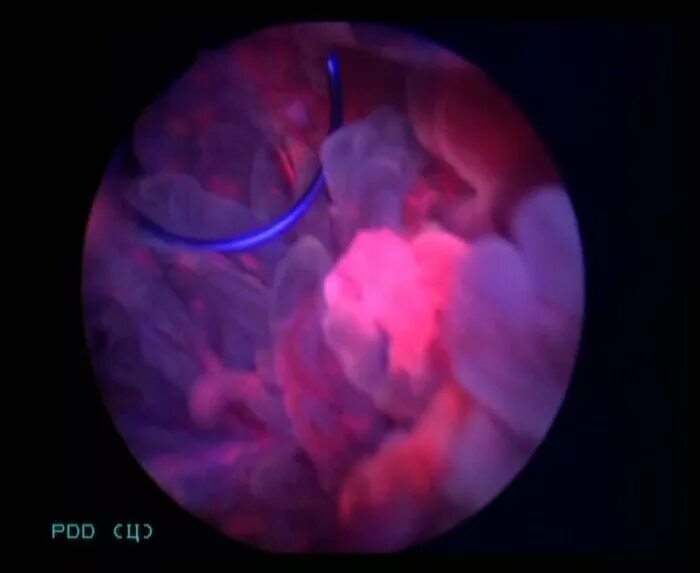

Фдт при дисплазии